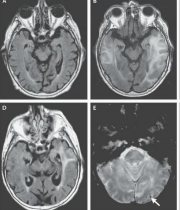

Un equipo de neurocientíficos, liderados por investigadores de la Clínica Mayo de Jacksonville (EE.UU.,) descubrió el gen responsable de un desorden cerebral que "puede ser mucho más común de lo que se piensa" y que puede provocar la muerte entre los 40 y 50 años de quienes lo padecen.

ImagenEse centro médico detalló en un comunicado que el equipo identificó 14 mutaciones diferentes del gen CSF1R que llevaron al desarrollo de leucoencefalopatía hereditaria difusa con esferoides (HDLS, por su sigla en inglés).